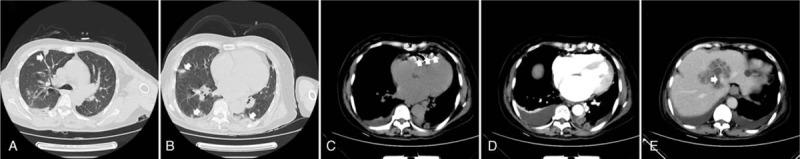

The chest computed tomography (CT) revealed multiple peripheral nodules in both lungs and wedge-shaped peripheral infiltrative lesions abutting the pleura, suggestive of septic pulmonary embolism. An abdominal CT on the following day showed a large liver abscess without gas formation and pneumocardia of the right ventricle.

胸部计算机断层扫描(CT)显示双肺多发外周结节及紧邻胸膜的楔形外周浸润性病变,提示脓毒性肺栓塞。次日腹部CT显示一个巨大肝脓肿,无气体形成,右心室积气。